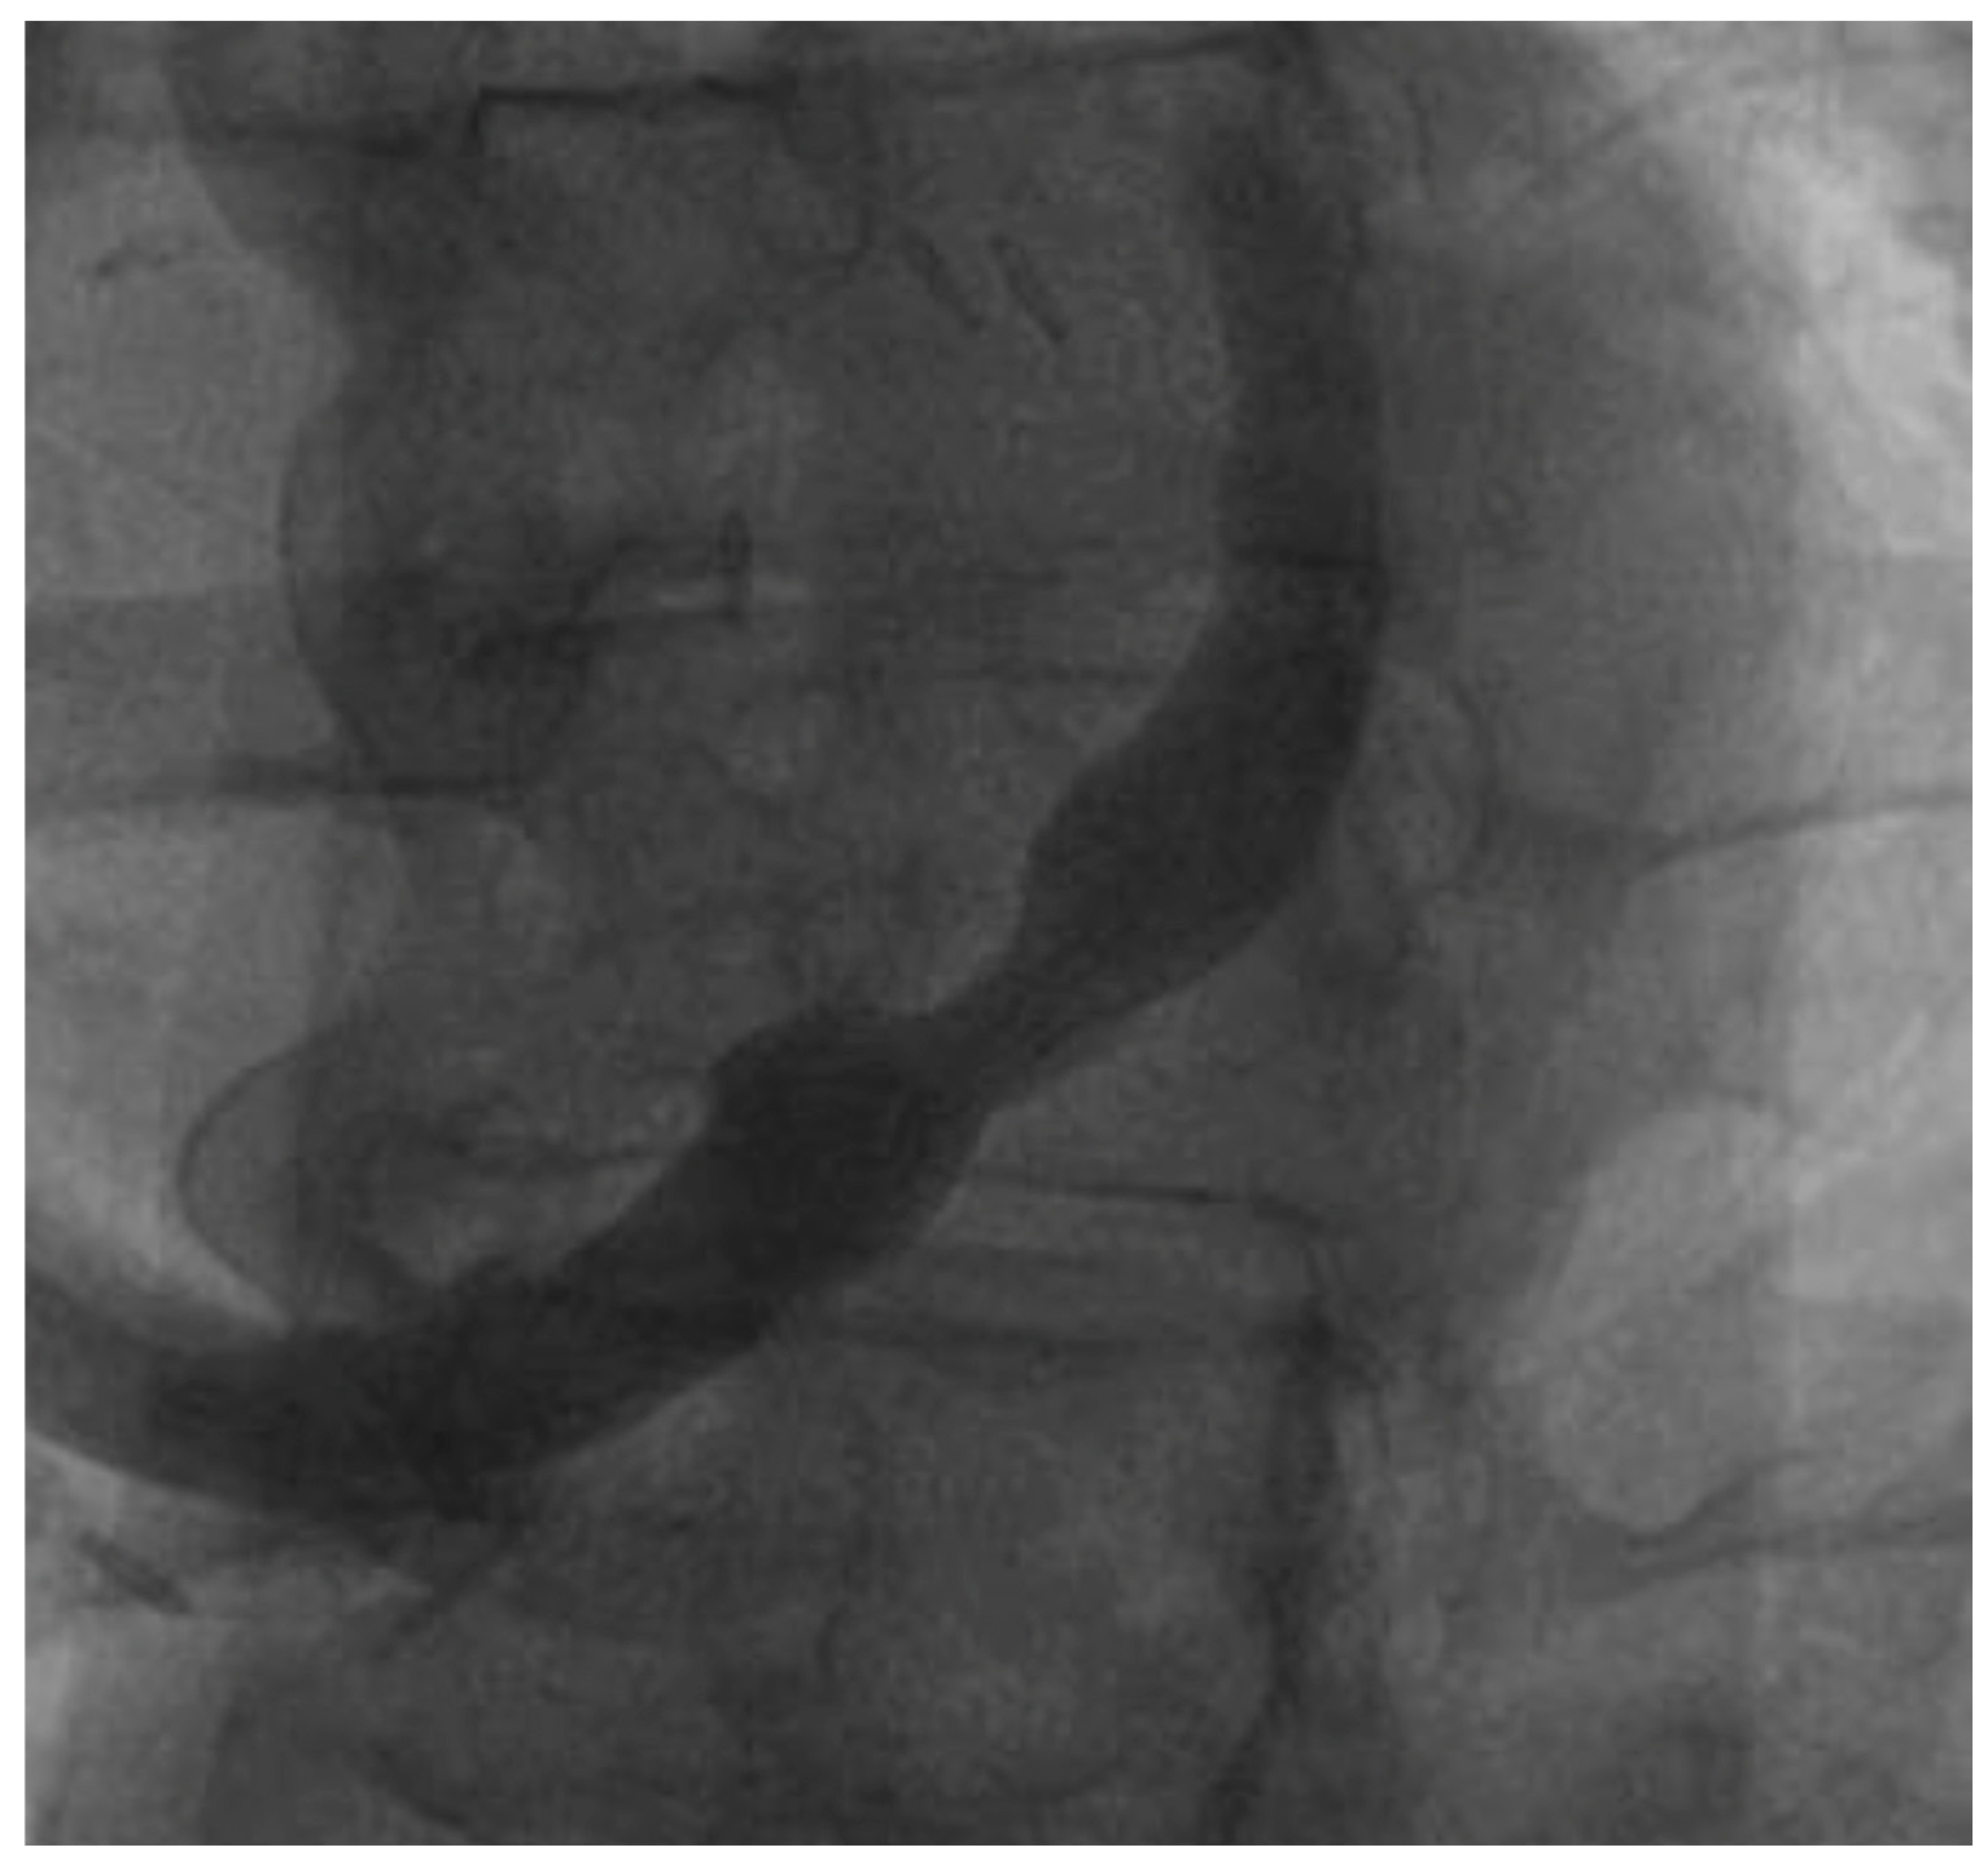

- Tebaldi, M.; Campo, G.; Ugo, F.; Guarracini, S.; Marrone, A.; Clò, S.; Abdirashid, M.; Di Mauro, M.; Rametta, F.; Di Marco, M.; et al. Coronary Sinus Narrowing Improves Coronary Microcirculation Function in Patients with Refractory Angina: A Multicenter Prospective INROAD Study. Circ. Cardiovasc. Interv. 2024, 17, e013481. [Google Scholar] [CrossRef]

- Servoz, C.; Verheye, S.; Giannini, F.; Banai, S.; Fradi, M.; Cuenin, L.; Bellemain-Appaix, A.; Gilard, M.; Benamer, H.; Adjedj, J. Impact of coronary sinus reducer on absolute coronary blood flow and microvascular resistance. Catheter. Cardiovasc. Interv. 2024, 104, 58–60. [Google Scholar] [CrossRef]